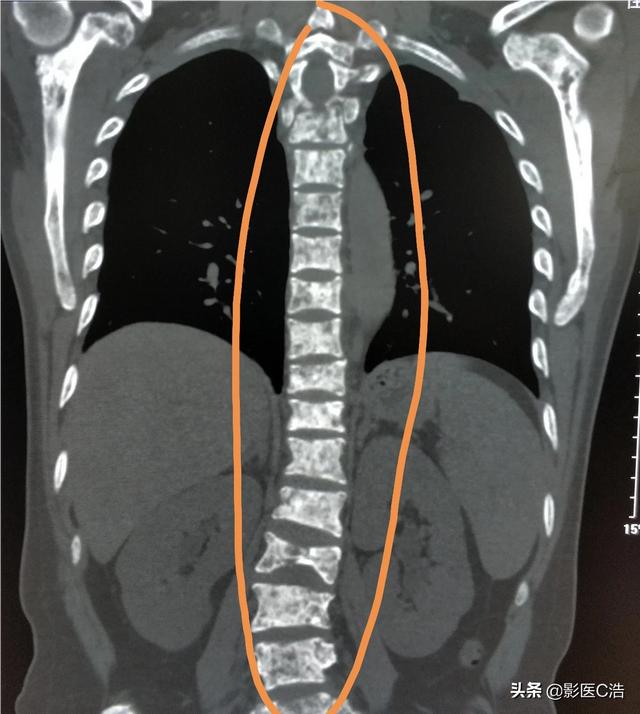

Quel type de douleur doit alerter sur la présence de métastases osseuses ? Les métastases osseuses sont une manifestation fréquente des tumeurs malignes à un stade avancé. La tumeur primaire présente dans d'autres parties du corps se métastase dans les os par les voies sanguines et lymphatiques, formant ainsi des métastases osseuses. Les métastases osseuses signifient que le tissu osseux normal a été détruit et remplacé par du tissu tumoral. Les métastases osseuses peuvent être classées en trois types selon la spécificité de la lésion : le type ostéolytique, le type ostéogénique et le type mixte. Les sites courants de métastases osseuses sont l'os de la diaphyse moyenne (colonne vertébrale et bassin), les côtes et la métaphyse inférieure, l'os de la diaphyse moyenne étant le plus courant, ce qui est lié aux caractéristiques de l'apport sanguin dans cette zone. Comme le montre le cercle ci-dessous, les métastases osseuses sont multiples et la colonne vertébrale est en mauvais état.

Montrant un cancer avec métastases osseuses survenant dans la colonne vertébrale thoracique